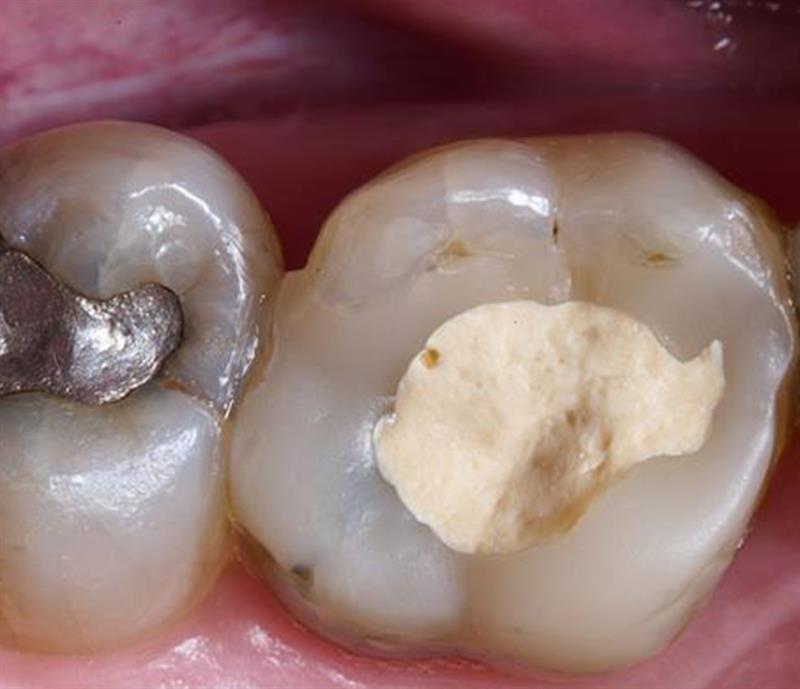

Bio-Bulk Fill procedure with Biodentine for deep cavity restoration

In this case study, Dr. Renner showcases the dual therapeutic and restorative properties of Biodentine™ for the restoration of a deep, subgingival cavity following a partial pulpotomy with the Bio-Bulk Fill procedure.

Click below to discover how he uses Biodentine™ for the successful treatment of a deep carious lesion with moderate pulpitis.